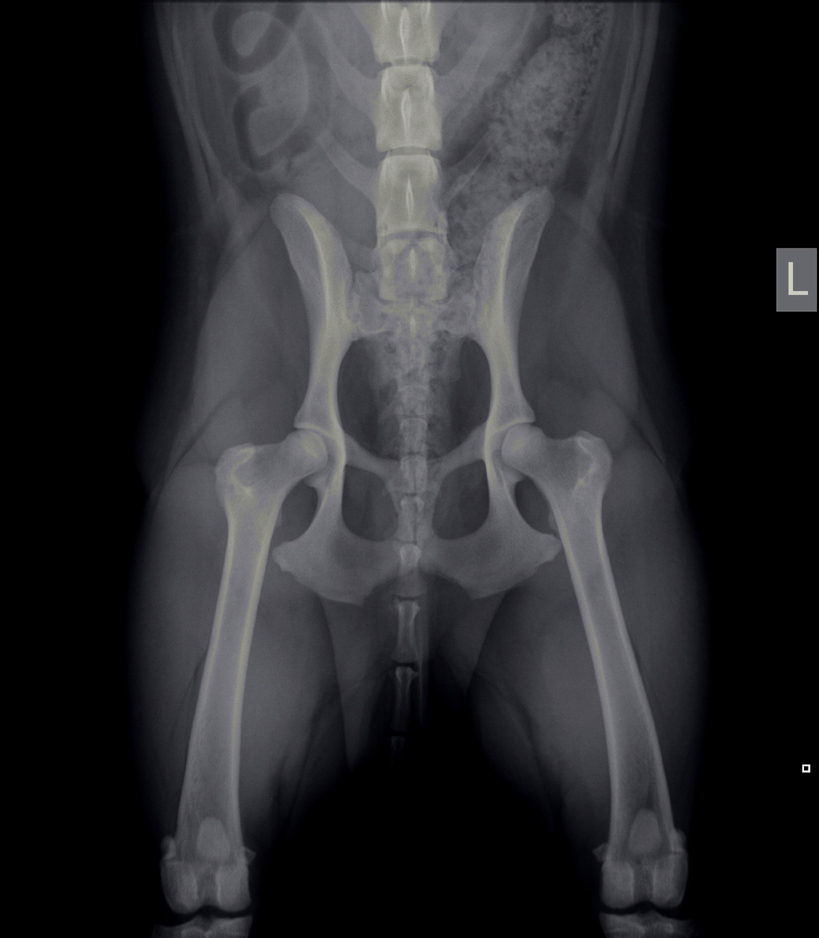

Heupdysplasie (HD)

Onder heupdysplasie wordt het volgende verstaan: een te ondiepe heupkom, waardoor de heupkop te veel ruimte heeft om te bewegen. Er is niet één enkele oorzaak voor te geven; meestal is het een combinatie van snelle groei, inspanning, voeding, leefomstandigheden en erfelijke factoren. Bij erfelijke factoren bestaat een aangeboren dysbalans tussen de spieren van het heupgewricht en de groei van bot, waardoor de heupkop niet goed in de kom wordt getrokken. Wat volgt is een abnormale ontwikkeling van het heupgewricht, wat kan leiden tot instabiliteit en daardoor irritatie van het gewrichtskapsel en het kraakbeen op de heupkop met artrose (=slijtage) als eindresultaat.

Artrose aan de heupen uit zich in het algemeen in bothaakjes aan de heupkop, verbreding van de hals van de heupkop (= de aansluiting van de heupkop met de rest van het dijbeen), onregelmatigheden in het bot van de heupkom en luxatie van de heupkop ten opzichte van de heupkom (heup geheel of gedeeltelijk uit de kom).

Met behulp van röntgenfoto’s kan de diagnose worden gesteld.